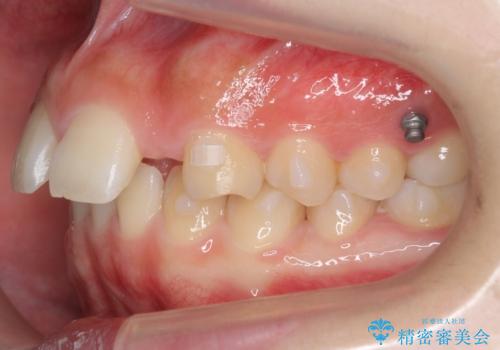

- 前歯の並びを主訴に来院。

前歯が出ており、また、左上の側切歯が1本生まれつき少ない状態でした。

また、右の奥歯の関係も上が前にある状態で大きくずれていました。

臼歯関係は無理に1級にしようとすると抜歯が必要になります。

今回は左右とも1歯対2歯の関係であるため、それは変えずに前歯を可及的にひっこめて足りない部分をブリッジで補う治療としました。

矯正後の前歯ブリッジについては横浜桜木町歯科の大元院長が担当しています。

奥歯の関係を完全に1級にするには右上の小臼歯の抜歯が必要でしたが、もともと左上の前歯が生まれつき少ないため今回は歯を抜かずに治療しています。